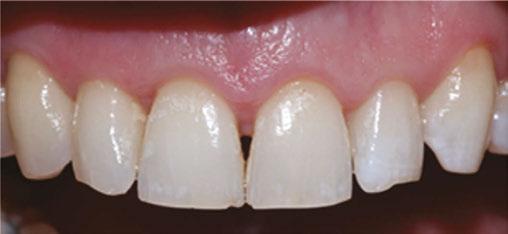

Patient A.M., age 28, presented with excessive gingival display she wished to correct (Figure 3). She lives in Boston and was willing to travel 3 hours each way to our practice in Queens,

New York. Multiple orthodontists near her home had prescribed surgical intervention for her case, but she had seen a gummy smile patient of mine treated nonsurgically and was excited about the prospects for herself (Instagram @NYCorthodontist).

Mesocephalic in CL 1 occlusion with slight constriction in the posterior areas. The patient’s facial and cephalometric analysis appeared normal, and her facial thirds were well balanced. Looking closely at the Digital Smile Design Analysis (Figure 3), we can appreciate the excessive gingival display, ranging between 4 mm-6 mm in the posterior and 3 mm-4 mm in the anterior.